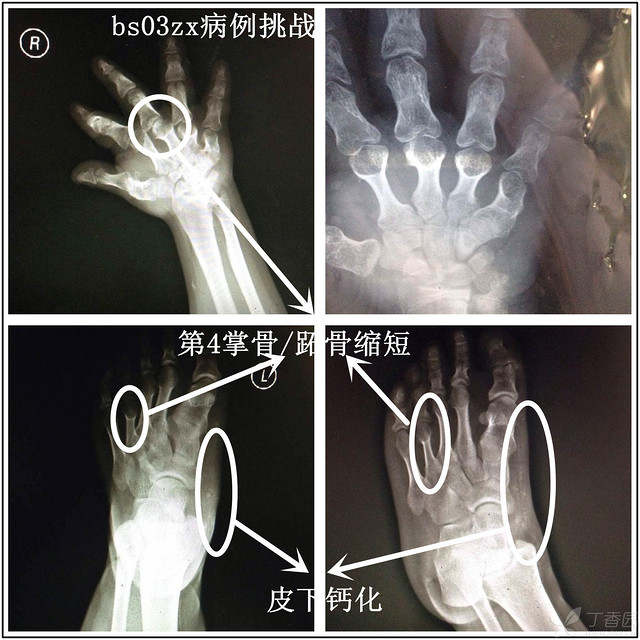

【bs03zx病例挑战】骨骼惊奇的少年,你能维护世界和平吗?

2.典型AHO体征(身材矮小、肥胖、圆脸、第4掌骨/跖骨缩短、皮下钙化)

此外,该患者除了存在手足部皮下软组织钙化,头颅CT示顶部脑表面及大脑镰旁多发钙化,头皮下软组织内多发钙化。